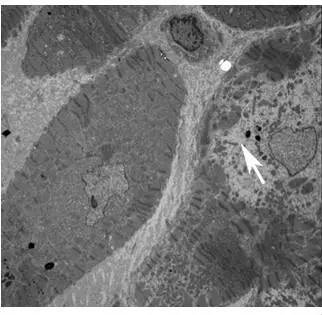

冠状动脉造影结果虽然明确提示存在冠心病,但前降支第一对角支和右冠状动脉后降支的狭窄不能解释左心室扩大和收缩功能重度减低。因患者存在IgGκ型M蛋白,故考虑浆细胞克隆性疾病,但后续检查未发现多发性骨髓瘤、浆细胞白血病、POEMS综合征等疾病相关证据。但轻链型系统性淀粉样变不能排除,该病可累及全身多系统包括心脏、肾脏、神经系统等。心肌淀粉样变的典型表现如下:心电图表现为QRS波低电压或假性心肌梗死样改变(如胸导联病理性Q波),可合并束支传导阻滞及多种类型心律失常。超声心动表现为左心室壁均匀增厚,心肌回声颗粒样增强,LVEF轻度降低,限制性舒张功能障碍,双心房增大,多数左心室腔不大或偏小,有些患者晚期可出现左心室扩大,LVEF明显下降。心肌磁共振表现为弥漫性片状延迟强化。其他系统表现包括眶周瘀斑、舌体肥大、大量蛋白尿、水肿、体位性低血压等,肌电图可提示神经源性损害。明确诊断需行骨髓、齿龈、舌体及腹壁脂肪活检,如发现淀粉样物质沉积即可确诊。本例患者虽然存在血清M蛋白,但心电图、心脏结构改变及心脏磁共振均非典型心肌淀粉样变表现,淀粉样物质沉积的其他系统表现亦不典型:无肾、肝、脾等脏器受累,肌电图异常仅 局限在上肢,并可用颈椎病来解释。体位性低血压可为系统性淀粉样变植物神经受累的特征表现,但是部分心力衰竭患者也会出现。进一步完善骨髓、齿龈、舌体及腹壁脂肪活检仅发现腹壁脂肪刚果红染色弱阳性。故诊断轻链型系统性淀粉样变证据不足,下一步应行心内膜活检。行心内膜活检,过程顺利;光镜病理(HE染色):部分心肌细胞肥大,排列紊乱,部分心肌细胞核增大,未见明确细胞坏死,间质纤维组织轻度增生,细胞间可见个别散在炎细胞浸润,心内膜下及小动脉壁见极少许粉染物,刚果红染色(局灶+),高锰酸钾化刚果红(-)。电镜:可见大量心肌细胞溶解坏死,细胞间闰盘结构破坏,线粒体变形,未见类淀粉蛋白细纤维聚集(图2)。

图2 电镜(心内膜活检病理)可见心肌细胞溶解坏死(A:箭头所示),细胞间闰盘结构破坏,线粒体变形(B:箭头所示)